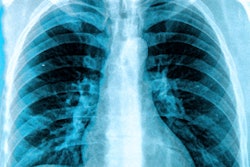

A keynote delivered by Curtis Langlotz, MD, PhD, professor of radiology, medicine, and biomedical data science at Stanford University, summarized that AI algorithms can assist radiologists at every step of the imaging process.

"There are aids that can provide inputs to help decide which imaging tests to order; programs to enhance image quality, making it possible to reduce radiation doses used in imaging; tools that instantaneously detect imaging problems to ensure that faulty images are retaken right away; applications that conduct basic triage to identify cases that may need immediate attention; and virtual assistants that help with reporting observations and following up with patients," Dartmouth shared in a blog post.

Langlotz's laboratory investigates the use of deep neural networks and other machine-learning technologies to detect disease and eliminate diagnostic errors through analysis of medical images and clinical notes. He also serves as associate director of Stanford’s Institute for Human-Centered Artificial Intelligence and as director of the Center for Artificial Intelligence in Medicine and Imaging.